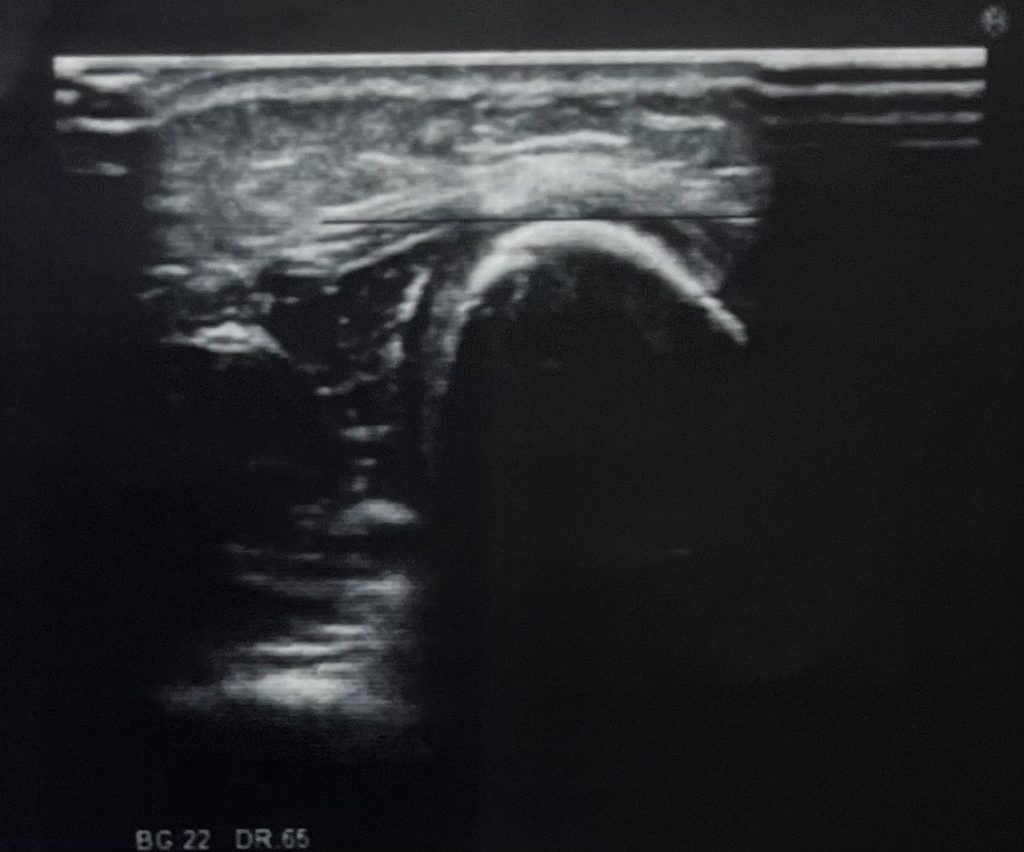

当初、打撲かなと思いきや、翌日来院も歩けない様なので、もう一度エコーで確認すると「骨折線」が見つかりました